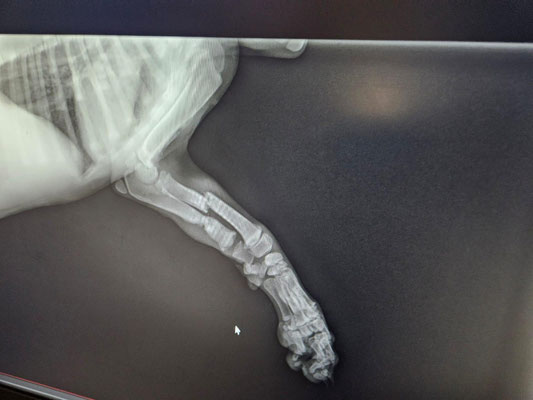

Im September 2025 haben wir Ihnen die kleine Finija vorgestellt: Gerade einmal vier Monate alt, wurde sie in einem erschütternden Zustand gefunden. Beide Hinterbeine waren gebrochen, eine Fortbewegung war für sie nur noch auf den Vorderpfoten möglich. Trotz starker Schmerzen zeigte Finija eine unglaubliche Willenskraft – ein kurzes Video aus…